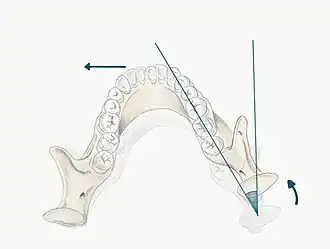

- Bimanual manipulation- manipulating the patient's condyles so they are in CR

- The operator should lightly rest their fingers along the inferior border of the mandible and their thumbs should lie lightly on the anterior aspect of the chin

- When the patient is relaxed place light downward pressure on the chin and light upward pressure under the angle of the mandible

- Deprogramme the jaw by guiding the opening and closing of the jaw and once the patient is relaxed, ask them to close gently and stop when they feel teeth first contacting

- Chin point guidance- one hand is used to apply pressure to the chin guiding the chin posteriorly with some force